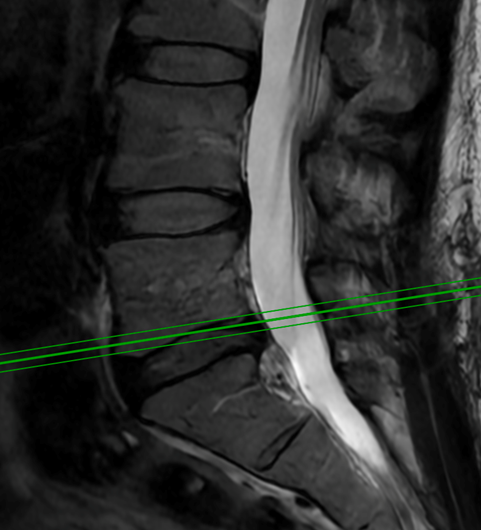

Spine:

Cervical Laminectomy and Fusion

Author: William Sonstein M.D., F.A.C.S., Read More!